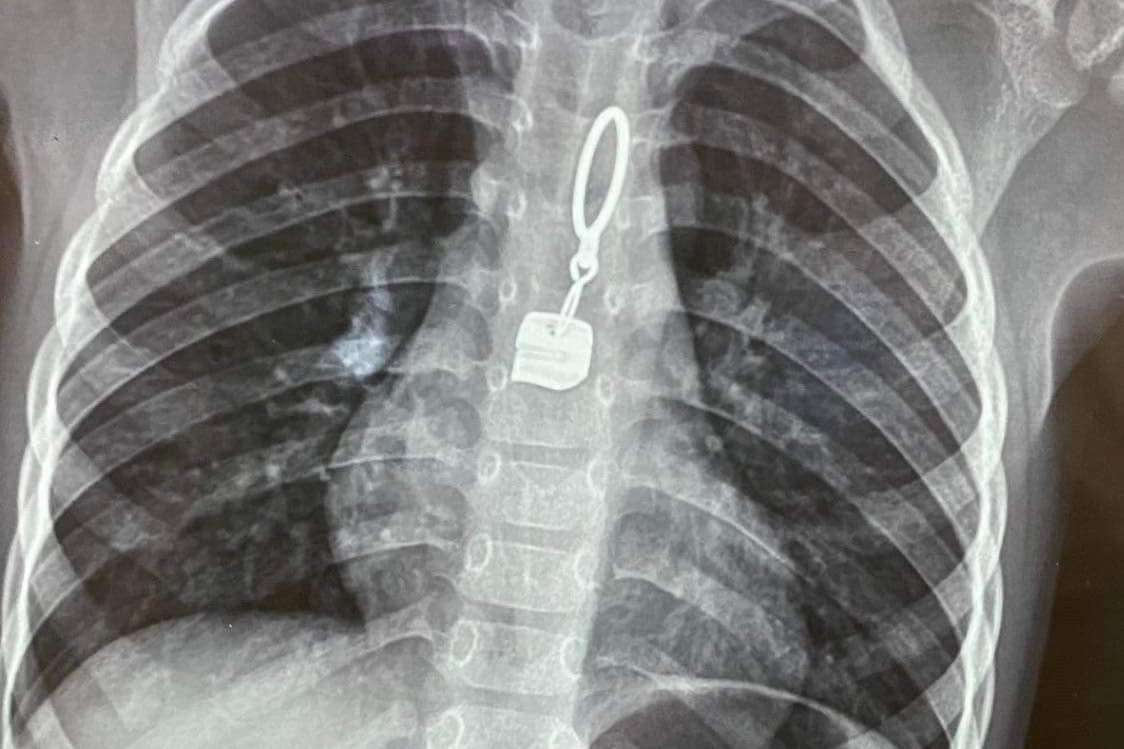

Phát hiện khóa kim loại trong thực quản bệnh nhi 3 tuổi